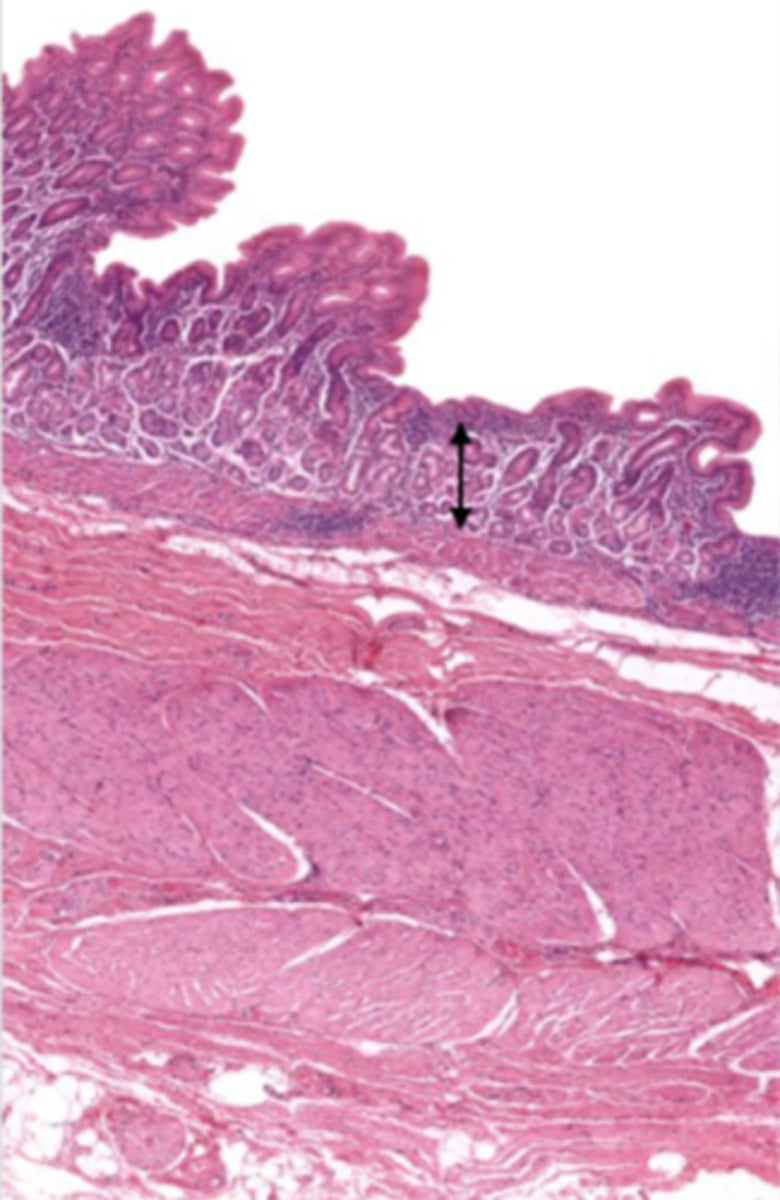

cardiac stomach (histology)

simple columnar epithelium

what kind of epithelium lines the mucosa of the cardiac stomach?

gastric pit (cardiac stomach)

lumen (cardiac stomach)

mucosa (cardiac stomach)

mucosal epithelium (cardiac stomach)

lamina propria (cardiac stomach)

muscularis mucosa (cardiac stomach)

submucosa (cardiac stomach)

contains glands and blood supply

muscularis externa (cardiac stomach)

serosa/adventitia (cardiac stomach)